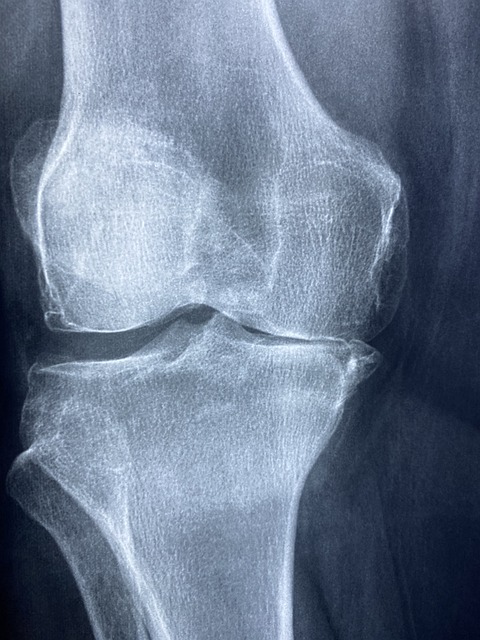

- 글루코사민 & 콘드로이틴

- 연골을 형성하는 성분으로, 관절의 윤활 작용을 돕고 연골 손상을 예방합니다.

- 특히 퇴행성 관절염 예방과 통증 완화에 효과적입니다.